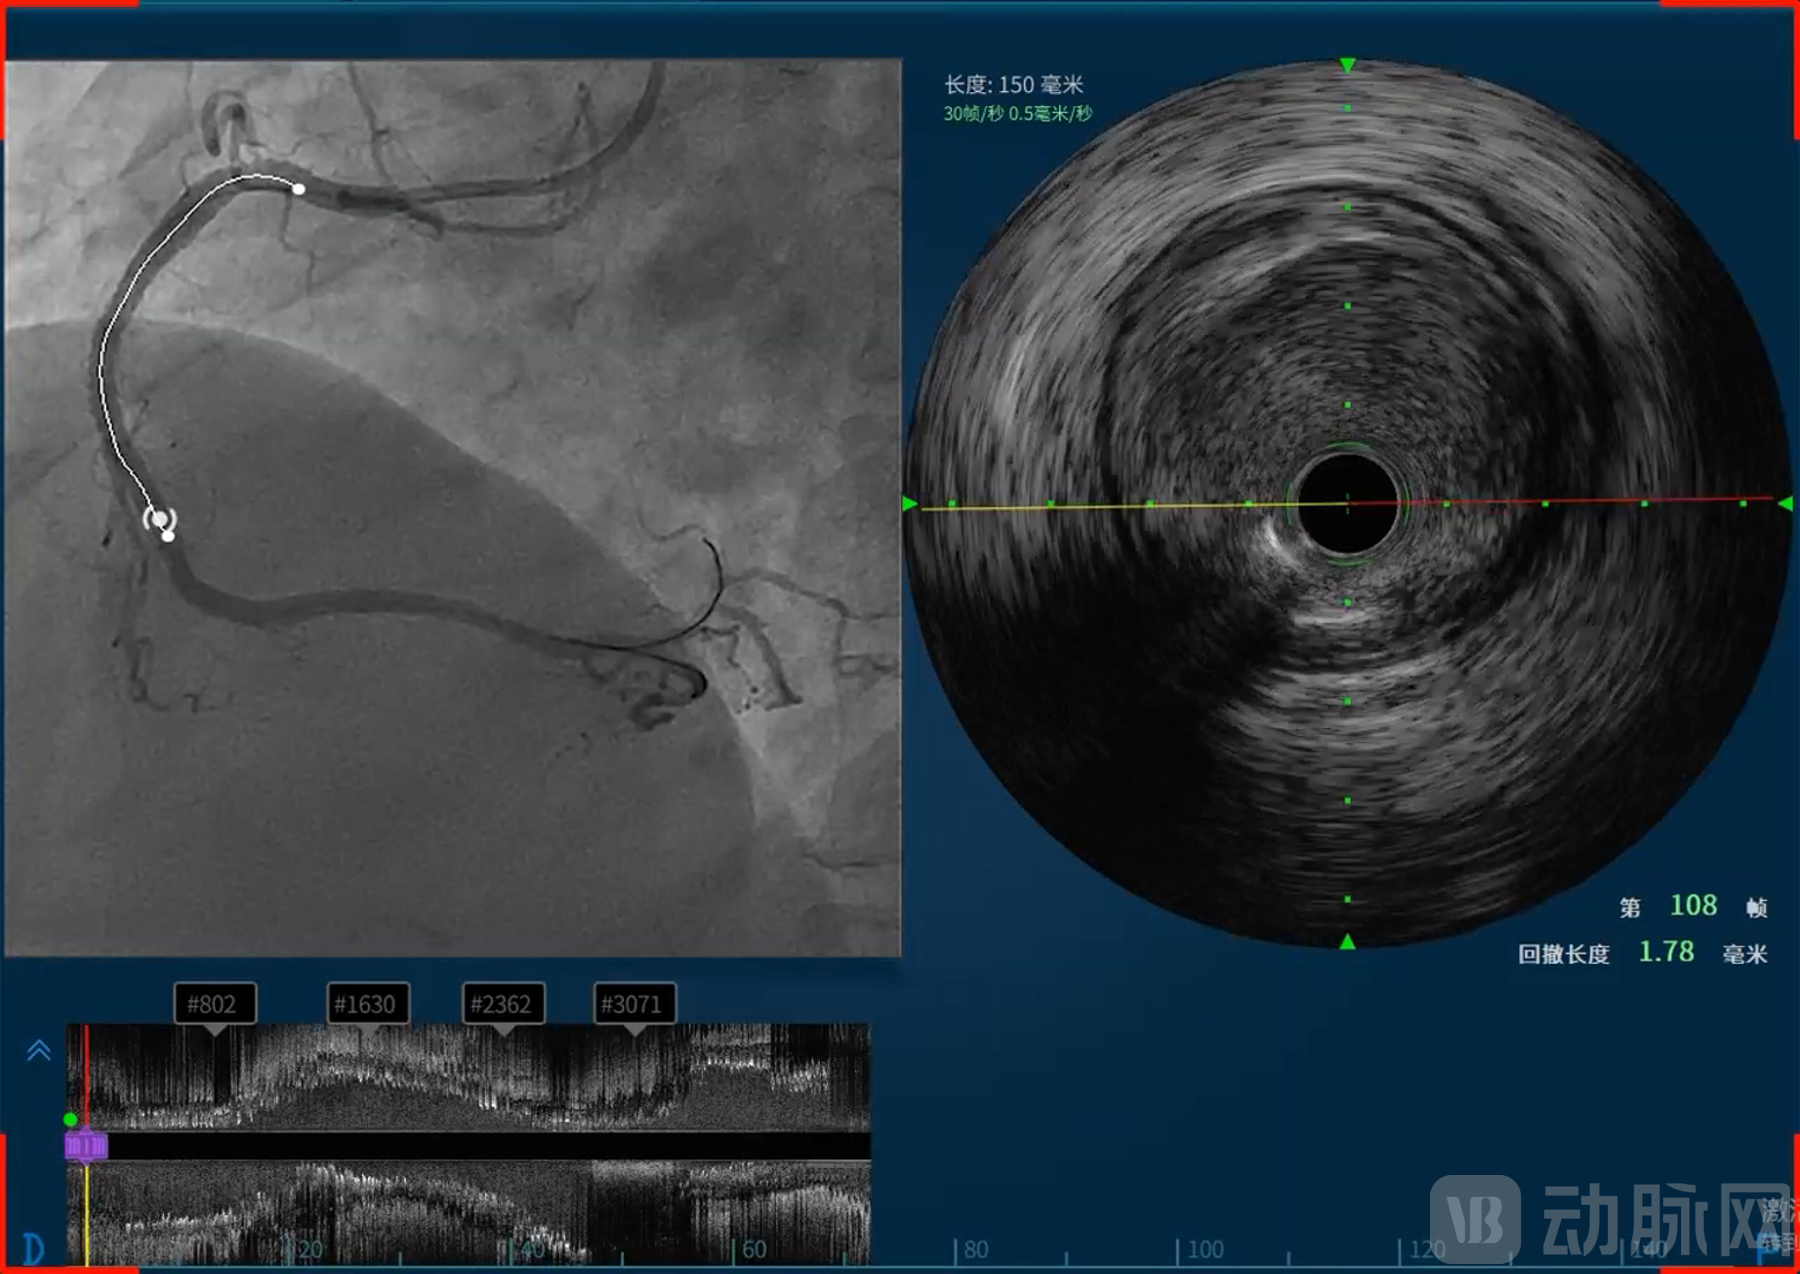

恒宇医疗的吸引力不仅在于所深耕的血管介入赛道,更在于其致力于构建的完整技术体系和难以复制的研发能力。恒宇医疗深耕血管内超声(IVUS)和光学相干断层成像(OCT)技术领域多年,形成了从核心元器件到整机设备,从单一产品到系统解决方案的全链条布局。恒宇医疗是国内少数同时掌握IVUS和OCT两项核心技术的企业,这种“双技术路线”并行的能力使其在血管介入精准诊疗领域占据了独特位置。

同时融合OCT与近红外光谱(Near-Infrared Spectroscopy, NIRS)的单光源双模态OCT-NIRS技术的成功,更使恒宇医疗成功建立了OCT/IVUS/NIRS三模态成像模式,为临床诊疗提供了更为全面的解决方案。

天津恒宇医疗成立于2016年,专注于血管内超声(Intravascular Ultrasound, IVUS)设备及导管、光学相干断层成像(Optical Coherence Tomography, OCT)设备及导管、IVUS/OCT一体机式的双导管系统、基于IVUS和OCT的无创血流储备分数(Fractional Flow Reserve, FFR)平台、融合OCT与近红外光谱(Near-Infrared Spectroscopy, NIRS)的单光源双模态OCT-NIRS技术及血管内激光斑块消蚀技术的自主研发、生产和销售,掌握光学、超声及导管平台技术,并不断基于底层技术进行全球领先的创新,致力于为医患提供以影像类产品为基础的泛血管一体化解决方案。